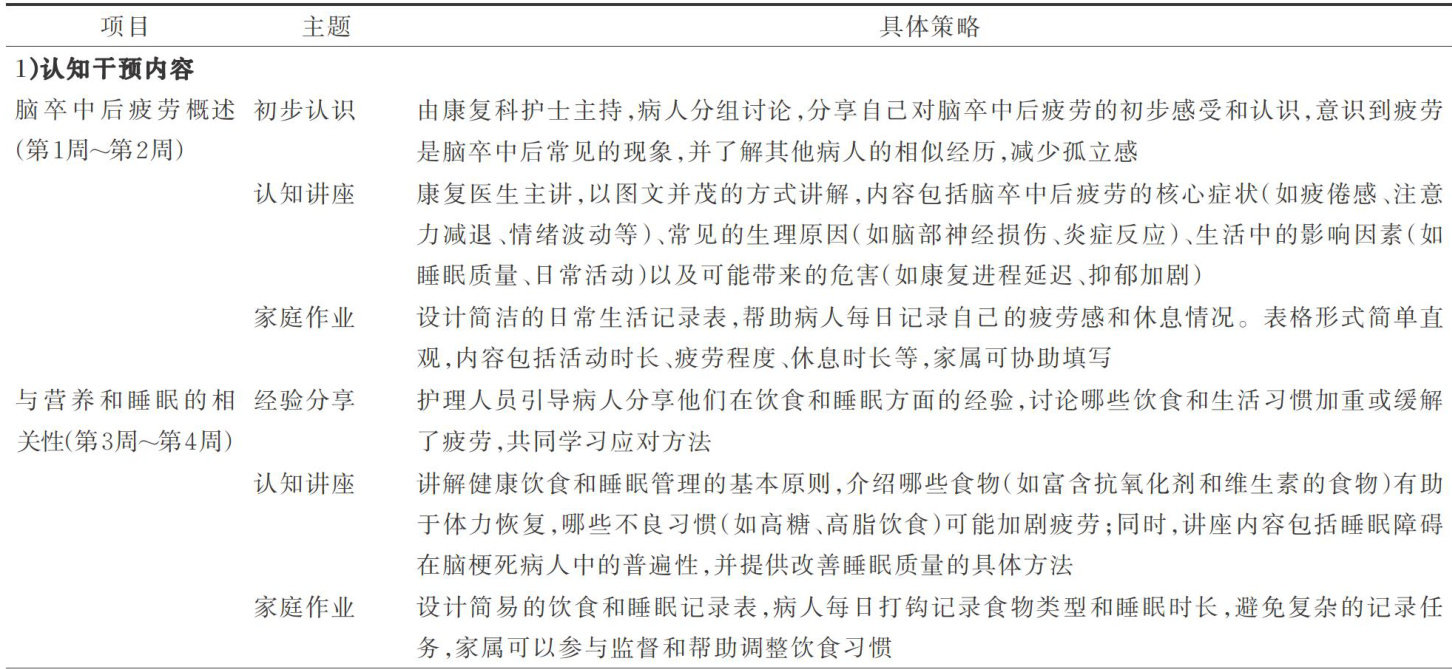

综合研究 | 基于老年脑梗死疲劳症状构建认知和分级活动训练康复方案的实证研究

综合研究 | 基于老年脑梗死疲劳症状构建认知和分级活动训练康复方案的实证研究